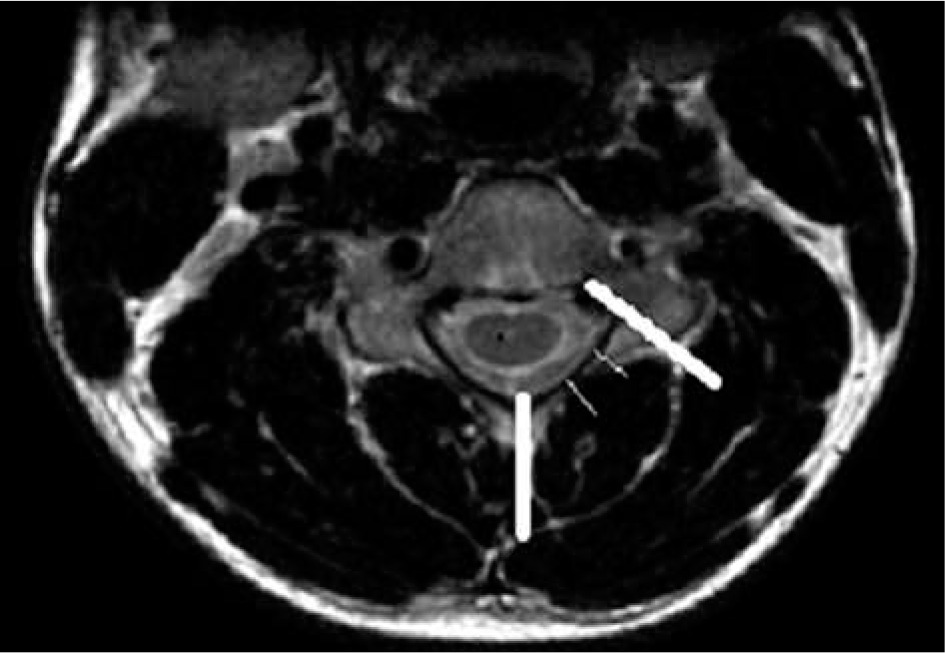

Figure 9

T2* axial section of the same patient in the neutral position showing loss of attachment from subjacent lamina, which is more than one-third and is better visualized than on T2W axial sections (arrow)